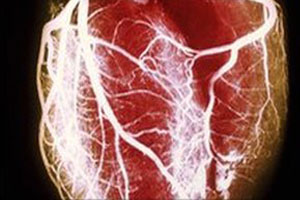

“We found that the association between one of your parents having a heart attack and you having a heart attack was a lot stronger than the association between your parent having a stroke and you having a stroke,” said senior author Peter M. Rothwell, M.D., Ph.D.